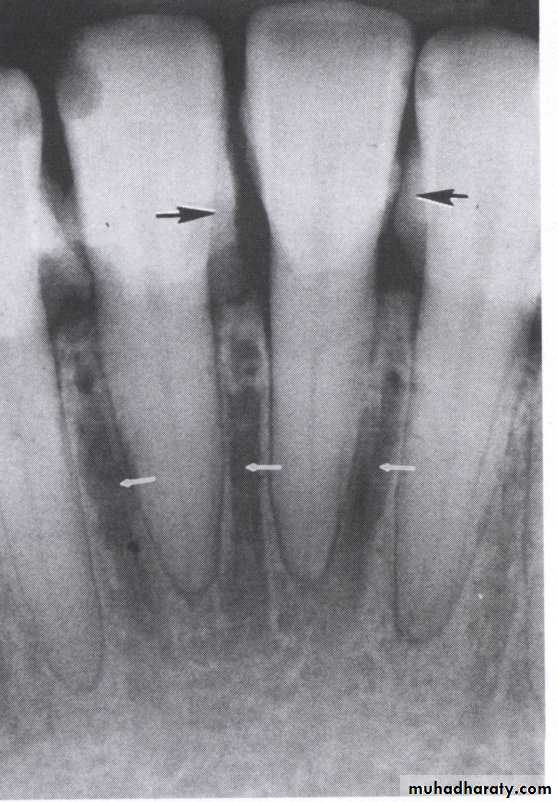

The normal alveolar crest lies 1 to 1.5 mm below the adjacent CEJs and forms a sharp angle with the lamina dura of the

adjacent tooth.

Between the anterior teeth the alveolar crest normally is pointed and well corticated.

Normal alveolar bone level is 1 - 1.5mm from CEJ.

Direction :

Intercrestal bone should be parallel with line dawn from the CEJ of one tooth to that of the contacting tooth.

1. Horizontal bone loss:- When loss occurs on a plane that is parallel with a line drown.

2.Vertical bone loss:- when there is greater bone loss in one tooth than on the adjacent tooth, so the bone level is not parallel with a line joining the CEJ.